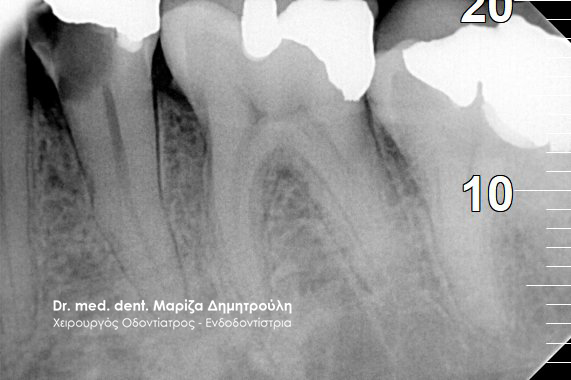

Η ασθενής προσήλθε με έντονο οίδημα στο πάνω δεξί μέρος του προσώπου. Παρόλο που είχε ξεκινήσει τη λήψη αντιβίωσης το οίδημα (πρήξιμο) δεν υποχωρούσε. Μετά την κλινική εξέταση διαπιστώθηκε έντονος πόνος στη ψηλάφιση και στην επίκρουση του δοντιού. Ακολούθησε η ακτινογραφική εξέταση του δοντιού, η οποία αποκάλυψε την ύπαρξη κατάγματος στο τελευταίο τριτημόριο της ρίζας του δοντιού. Δίπλα από το κάταγμα είναι εμφανής η αλλοίωση στο οστό (έντονη μαύρη σκιά).

Μετά από συζήτηση με την ασθενή αποφασίστηκε η εξαγωγή του δοντιού και η δημιουργία στεφάνης στο διπλανό δόντι με ένα κρεμαστό δόντι, το οποίο και θα αντικαθιστούσε το ελλείπον δόντι. Αυτή η λύση αποτέλεσε το εναλλακτικό σχέδιο θεραπείας, εφόσον βέβαια η ασθενής δεν επιθυμούσε την τοποθέτηση εμφυτεύματος.

ΠΡΙΝ

Ακτινογραφία – Κάταγμα στη ρίζα του δοντιού

META